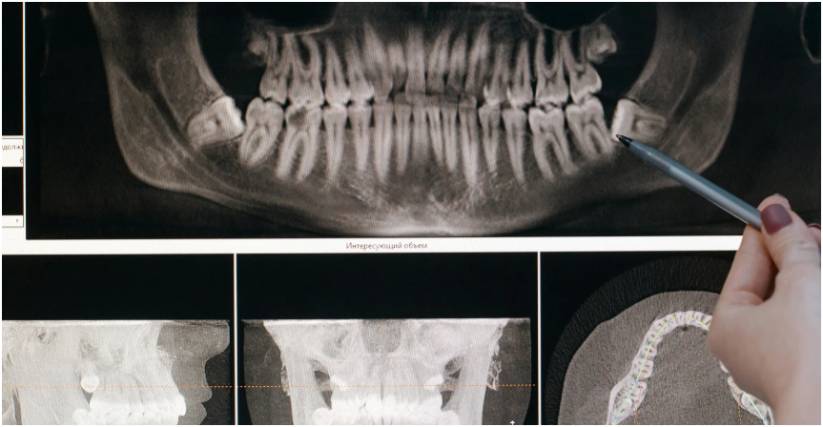

Your jawbone, specifically the alveolar bone, has a very specific purpose: to support and hold your teeth. It is a symbiotic relationship.

When you chew and bite, the roots of your teeth transmit physical stimulation to the jawbone. This stimulation signals the body to send nutrients to that area, keeping the bone dense, healthy, and strong.

Jawbone loss, also known as resorption, occurs when that stimulation ceases or when destructive bacteria attack the bone tissue.

1. Missing Teeth: When a tooth is extracted or lost due to trauma, the alveolar bone no longer receives the necessary stimulation from the tooth root. The body, efficient as it is, begins to view that portion of the bone as unnecessary.

Over time, the body reabsorbs the calcium and minerals from that section of the jaw, causing the bone to shrink in height and width. This process can begin almost immediately after a tooth is lost.

2. Periodontal Disease: This is a severe gum infection that damages the soft tissue and destroys the bone that supports your teeth. It is caused by plaque buildup that hardens into tartar.

As the bacteria multiply, they release toxins that break down the connective tissue and bone, leading to tooth loss and significant bone deterioration.